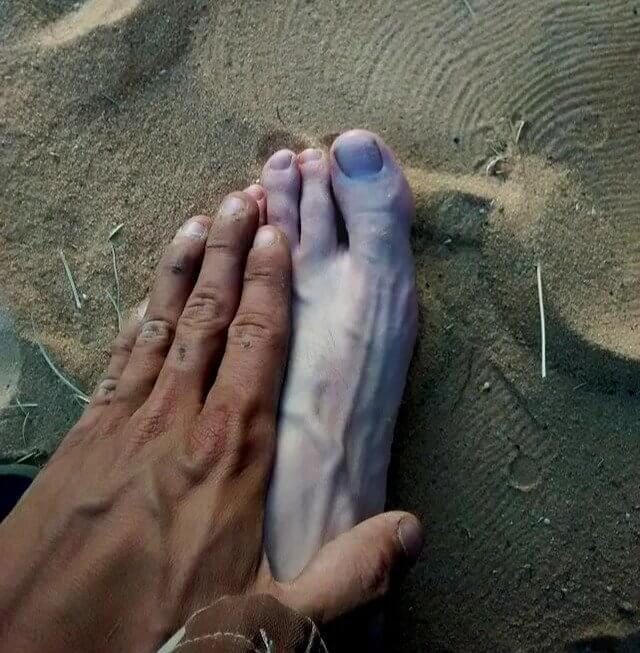

Same Person, Different Limbs

The person photographed here suffers from a condition called Raynaud's disease, which takes effect in cold temperatures or stress. Parts of the person's body, like their fingers and in this case, toes, start to feel numb and cold to the touch - and look halfway frozen if you ask us. Get this man a pair of warm socks, his big toe looks like it's about to freeze off. Yikes!

We're hoping not permanent damage is left after getting exposed to cold weather. It surely looks unpleasant enough as it is!